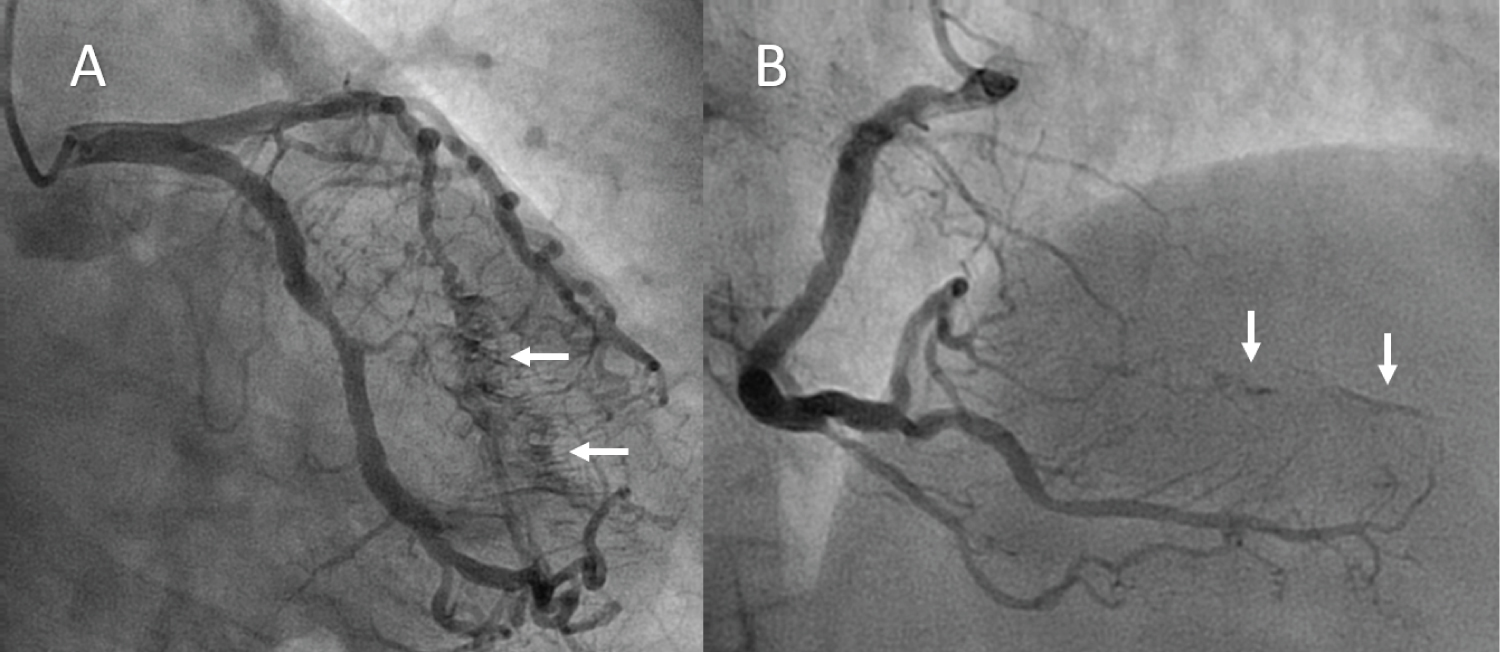

After medical treatment she underwent cardiac catheterization within the first 24 hours from the onset of symptoms. It showed diffuse non-obstructive coronary lesions and severe stenosis of mid segment of left anterior descending artery, which was treated with stent implantation. Coronary arteriography also revealed the presence of multiple fistulae originating from both the left coronary artery system and the right coronary artery and draining into the left ventricular cavity (white arrows in Figure 2A and Figure 2B).

Figure 2: Coronary arteriography revealed the presence of multiple fistulae (arrows) originating from both the left coronary artery system A) and the right coronary artery; B) and draining into the left ventricular cavity. View Figure 2